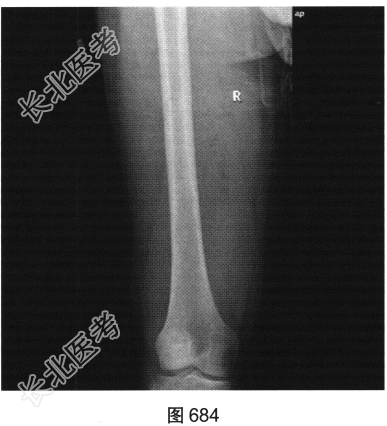

- 多项选择题2.[提示]患者X线检查见图684、图685。从以上X线平片中可以发现哪些异常表现( )

A、右股骨骨髓腔内未见明显异常密度影

B、右侧股骨形态可,可见骨质破坏

C、右大腿后方肌群软组织肿块边界清楚,密度均匀,未侵犯邻近骨质结构

D、右大腿后方肌群广泛水肿

E、右大腿后方肌群软组织肿胀,可见肿块影

F、右大腿软组织内密度不均匀增高